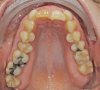

Das Quietschen fällt mir schon gar nicht mehr auf. Aber ich trage sie weiterhin fleißig. Ich kann schon sagen, dass sich der Zahn, gut eingestellt hat. Vor vier Monaten konnte ich noch die Kaufläche mit meiner Zunge beim zubeißen erfühlen. Das geht jetzt nicht mehr. Ich schaue mal, ob ich gleich noch die Fotos meiner KFO vor der Behandlung und von vier Wochen hochladen kann. Da kann man den Unterschied schon gut erkennen. Was ich als Laie halt so sagen kann. Außerdem habe ich das Gefühl, dass mein rechter vorderer Eckzahn etwas mehr Platz hat und nicht mehr so weit nach vorne steht.

Okklusion_rechts-Anfangsdiagnostik-2023_09_20-0_2[1].jpg Okklusion_Anterior-Anfangsdiagnostik-2023_09_20-0_1[2].jpg Okklusion_links-Anfangsdiagnostik-2023_09_20-0_3[1].jpg Okklusion_OK-Anfangsdiagnostik-2023_09_20-0_4[1].jpg Okklusion_UK-Anfangsdiagnostik-2023_09_20-0_5[1].jpg DSC_7646[1].JPG DSC_7649[1].JPG DSC_7651[1].JPG DSC_7652[1].JPG DSC_7655[1].JPG

Ich hoffe, ihr könnt auf diesen Bildern die Entwicklung sehen.